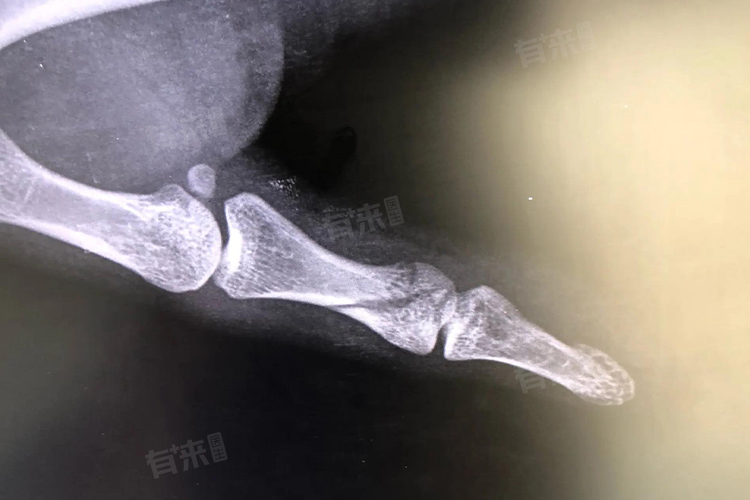

- 小拇指轻微骨裂的恢复还与骨裂的位置和类型有关,如果骨裂是单纯的线性骨折,没有明显的移位,自行恢复的可能性较大,这种情况下,只要保持骨折部位的稳定,避免过度活动,骨骼通常能够逐渐愈合,但如果骨裂是粉碎性骨折,或者伴有明显的移位,自行恢复的难度就会增加,此时可能需要进行手术复位和固定,以确保骨折部位能够正确愈合。